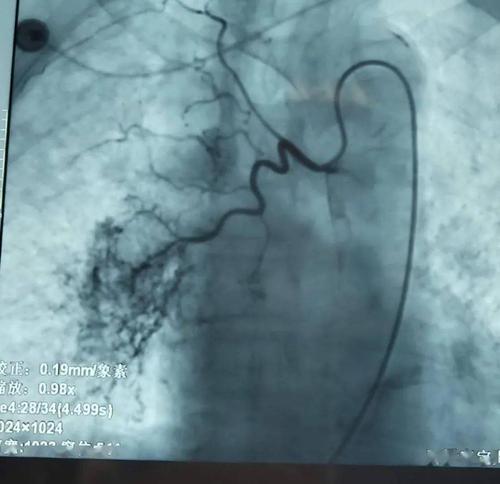

支气管动脉造影左下肺出血